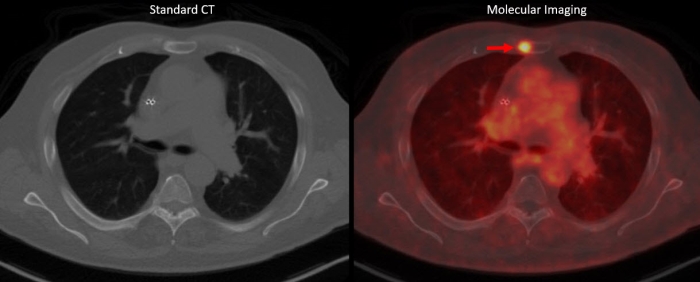

If the “key” is linked to a radioisotope that emits a small amount of radiation, the key can be used to detect and visualize where the cancer cells are in the body. That is molecular imaging. Below is a side by side comparison of traditional CT imaging on the left vs. molecular imaging on the right. Molecular imaging, which utilizes PET/CT imaging in combination with specially designed molecules that bind to targets on cancer cells, found cancer unlike traditional CT imaging.